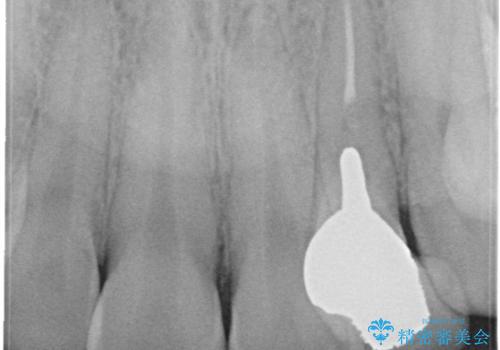

- 以前に被せ物の治療した箇所に汚れが溜まりやすいことを主訴に来院されました。

矯正治療を行なったのち、オールセラミッククラウンにて修復しております。

矯正治療はインビザラインで行なっております。